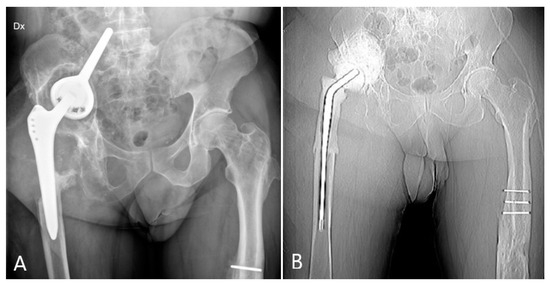

2.2. Case #2